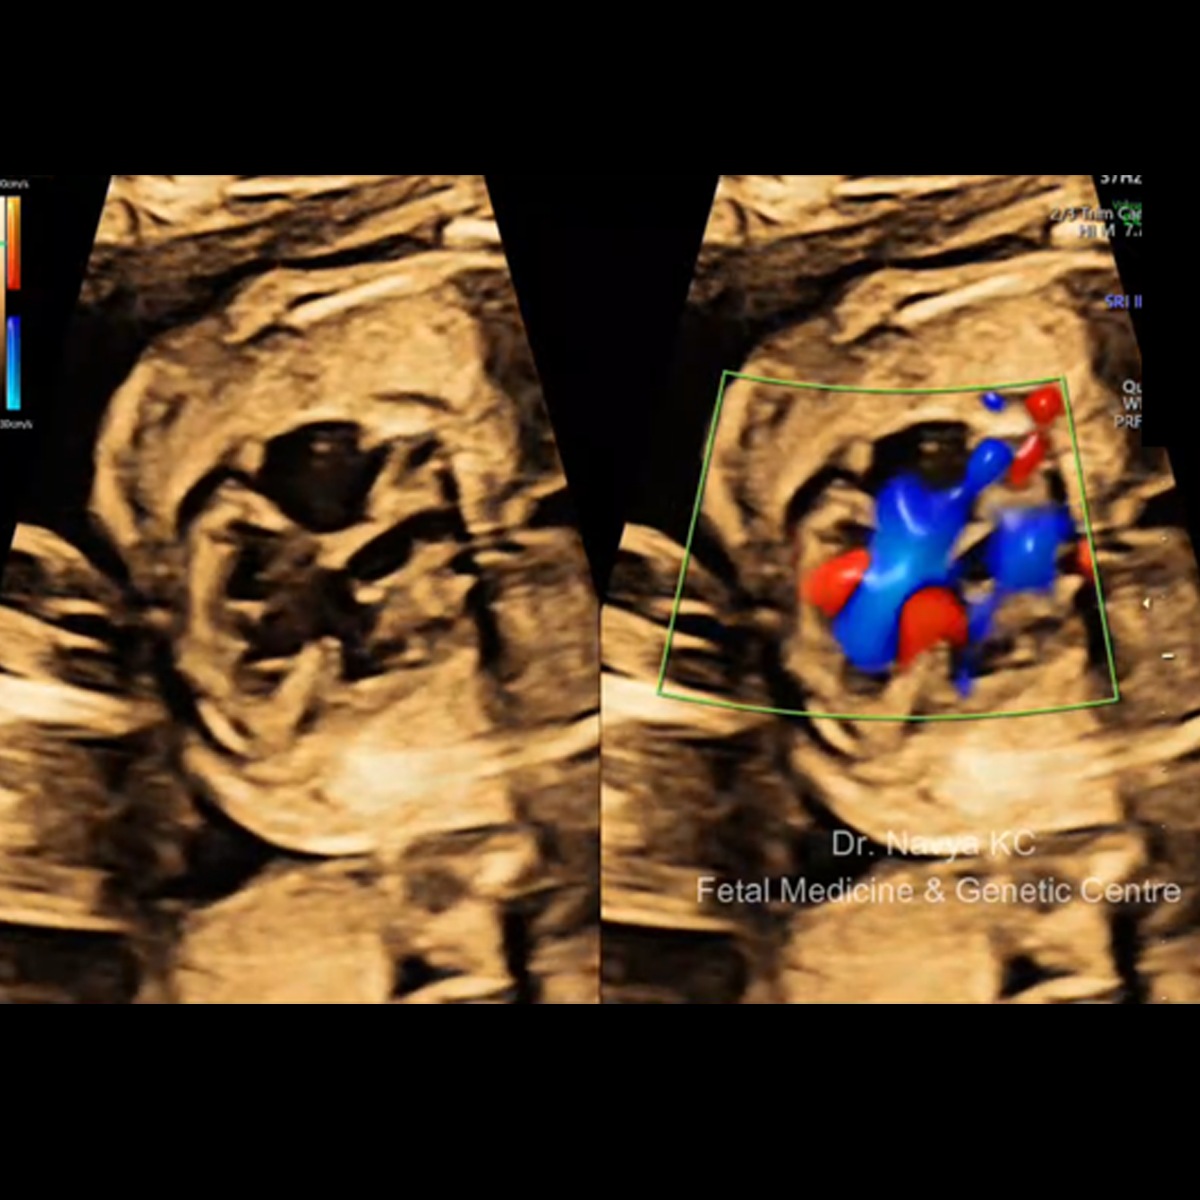

VI. Fetal Echocardiography (22-24 weeks):

Fetal Echocardiography is ideally done at 22-24 weeks, however, if malformation is suspected, can be performed at any time. Candidates for Fetal Echocardiography are: Suspected cardiac malformation, multiple pregnancy, obese women, previous baby/ pregnancy with cardiac malformation, family history of congenital cardiac disease, maternal diabetes, epilepsy, intake of medicines which increase risk for cardiac defects, eg, medicines for epilepsy.